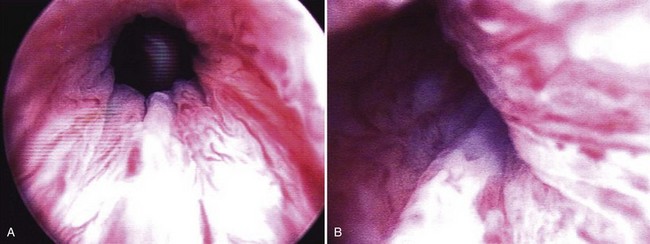

The materials can be administered under local anesthesia with cystoscopic control as an outpatient procedure. Both the periurethral and transurethral methods have been done to implant the agent within the urethral wall, preferably into the submucosa or lamina propria. It is thought that the implant should be positioned at the bladder neck or proximal urethra. Different sites can be chosen such as the 3- and 9-o’clock or 4- and 8-o’clock positions. The needle size depends on the viscosity of the agent. Preoperative and postoperative antibiotics are frequently administered. The technique of injection is seen in Figures 74-3 and 74-4. Additional bilateral periurethral infiltration of 2 to 3 mL of 1% or 2% aqueous lidocaine injected lateral to the urethra may improve patient comfort. The goal with current injectable agents is to create mucosal apposition at the end of treatment.

Figure 74–3 Periurethral collagen injection. The 20-Fr cystoscope with a 30-degree lens is positioned in the urethra while the substance is injected into the bladder neck region. A, Appearance of the urethra before treatment. B, Periurethral needle positioned in the proximal urethra below the bladder neck. C, Appearance of the urethra after injection.

(Reprinted with permission, Cleveland Clinic Center for Medical Art & Photography © 1994-2011. All Rights Reserved.)

Figure 74–4 A, Cystoscopic view of the open bladder neck region before injection. B, Collagen has been injected via the periurethral route on the patient’s left side. Note the intraluminal bulking effect of the bulking agent.